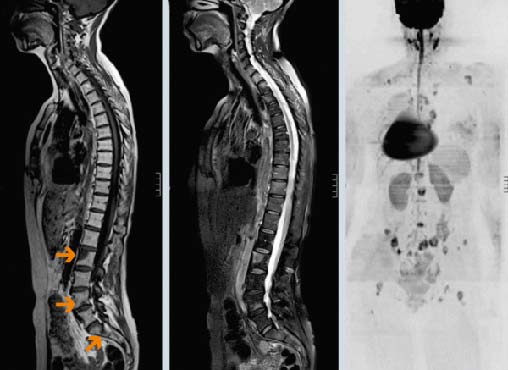

Диагностика метастазов в позвоночнике

Основные методы диагностики — КТ и МРТ. Они позволяют детально визуализировать структуры позвоночника и опухолевую ткань. Рентгенография менее информативна, так как показывает только костные структуры. Обычно ее используют при подозрении на патологический перелом.

Диагноз подтверждается биопсией. Врач получает фрагмент опухолевой ткани и отправляет его в лабораторию для цитологического и гистологического исследований, а также молекулярно-генетических анализов. Материал для биопсии может быть получен различными способами:

- Чаще всего проводят пункционную чрескожную биопсию с помощью иглы под контролем рентгена.